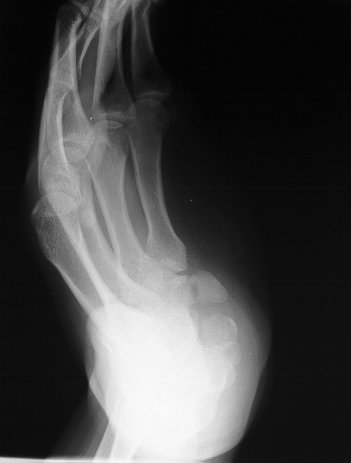

Clinical Example: Hook of hamate nonunion excision

Hook of hamate fractures are prone to nonunion, and their diagnosis is frequently delayed or missed. Cronic nonunions may result in flexor tendon rupure and other complications. Treatment for most patients is excision of the small fracture fragment.

This chronically painful nonunion was not visible on PA, lateral and oblique films, but can be seen clearly on this supinated oblique hamate hook view: